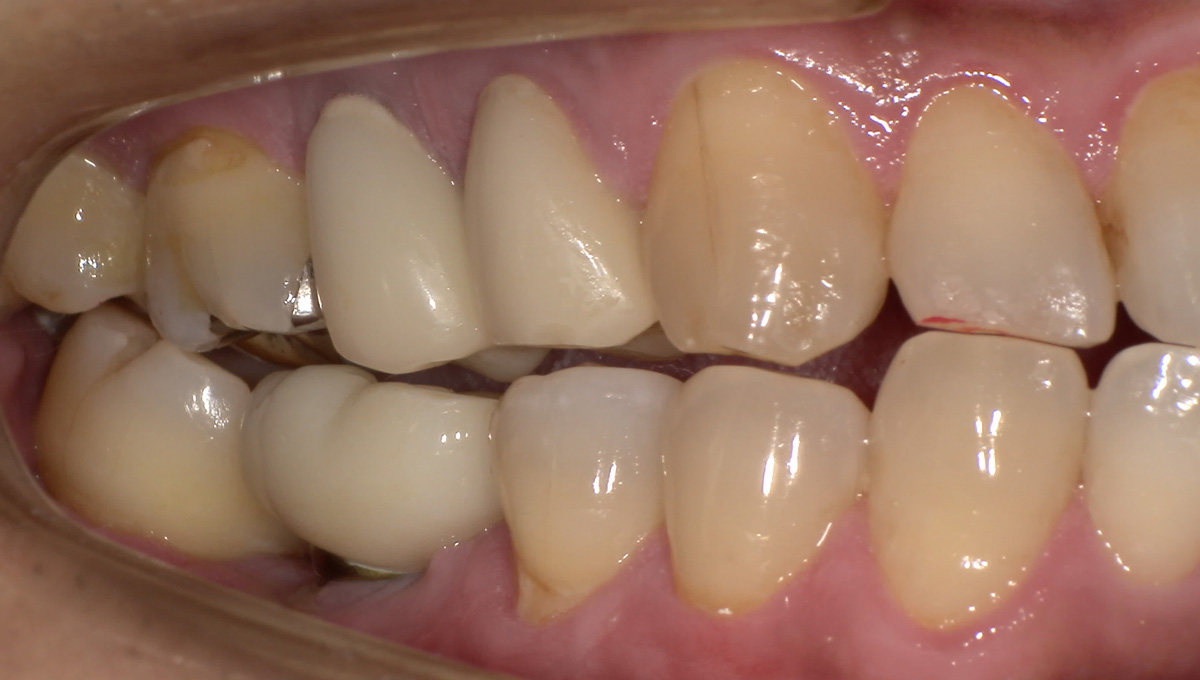

インプラント手術から3ヵ月後、型どりをして、仮歯を製作しました。

レントゲン画像 -

仮歯の調整期間を経て、セラミックの歯が入りました。

レントゲン画像 治療前 インプラント治療後

| 主訴 | 右下の歯が痛い。(抜歯後は、インプラント治療希望) |

| 診断 | 右下第一大臼歯 歯根膜炎 |